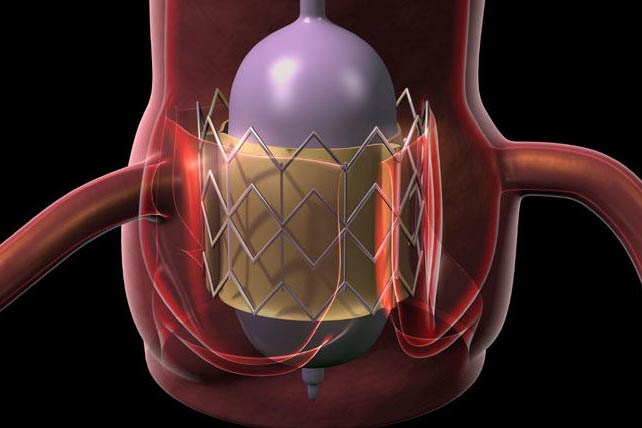

The Centre’s work builds on years of leadership in data-driven analytics and imaging. More recently, the Centre has added genomics to its core capabilities, opening new frontiers in precision health and personalized medicine. From predictive risk modeling to AI-powered diagnostics, the Centre focuses on finding solutions that make a difference in real lives, in real communities.

The Centre’s team is passionate about understanding the heart and how its size, shape, function, stiffness, and contractility, combined with genomic and environmental data, can predict the risk for heart attacks, stroke, and arrhythmias. With this insight, clinicians can intervene earlier and tailor care more effectively. It has the talent, data, infrastructure, and visionary leadership to make this future a reality.